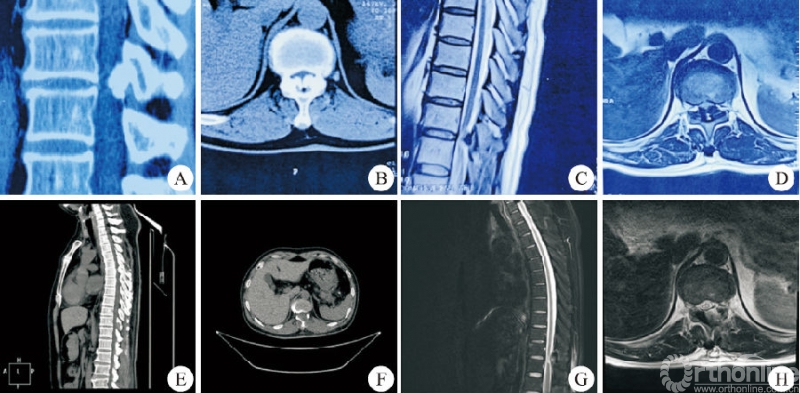

所有患者的手术由同一位术者完成,手术均顺利完成,无硬膜外血肿、切口感染及术后瘫痪者。37例患者中男14例,女23例;年龄31~82岁,平均(57.6±11.8)岁。上胸段(T1−T4)1例,中胸段(T5−T9)7例,下胸段(T10−T12)29例。24例采用俯卧位,13例采用侧卧位。平均住院时间(7.2±1.6)d,平均手术时长(96.5±20.0)min。平均出血量(41.9±10.8)mL。24例俯卧位手术患者均为OLF,做“漂浮”处理的3例,2例患者术中硬膜破裂(图3)。13例侧卧位手术患者中TDH3例,OPLL5例,OLF+OPLL5例,做“漂浮”处理的1例,2例患者术中硬膜破裂(图4)。术后影像学检查示椎管减压充分,致压物被完全去除。

男,46岁,T11−T12黄韧带骨化合并椎管狭窄,行俯卧位经皮内镜可视化环锯椎管减压术。A、B:术前CT矢状位和横断位示T11−T12融合型黄韧带钙化;C、D:术前MRI示脊髓严重受压合并信号改变;E、F:术后CT矢状位和横断位示钙化的黄韧带完全去除椎板充分扩大减压;G、H:术后MRI示脊髓不受压硬膜完全鼓起。图3 T11−T12俯卧位胸椎后入路术前与术后影像学资料